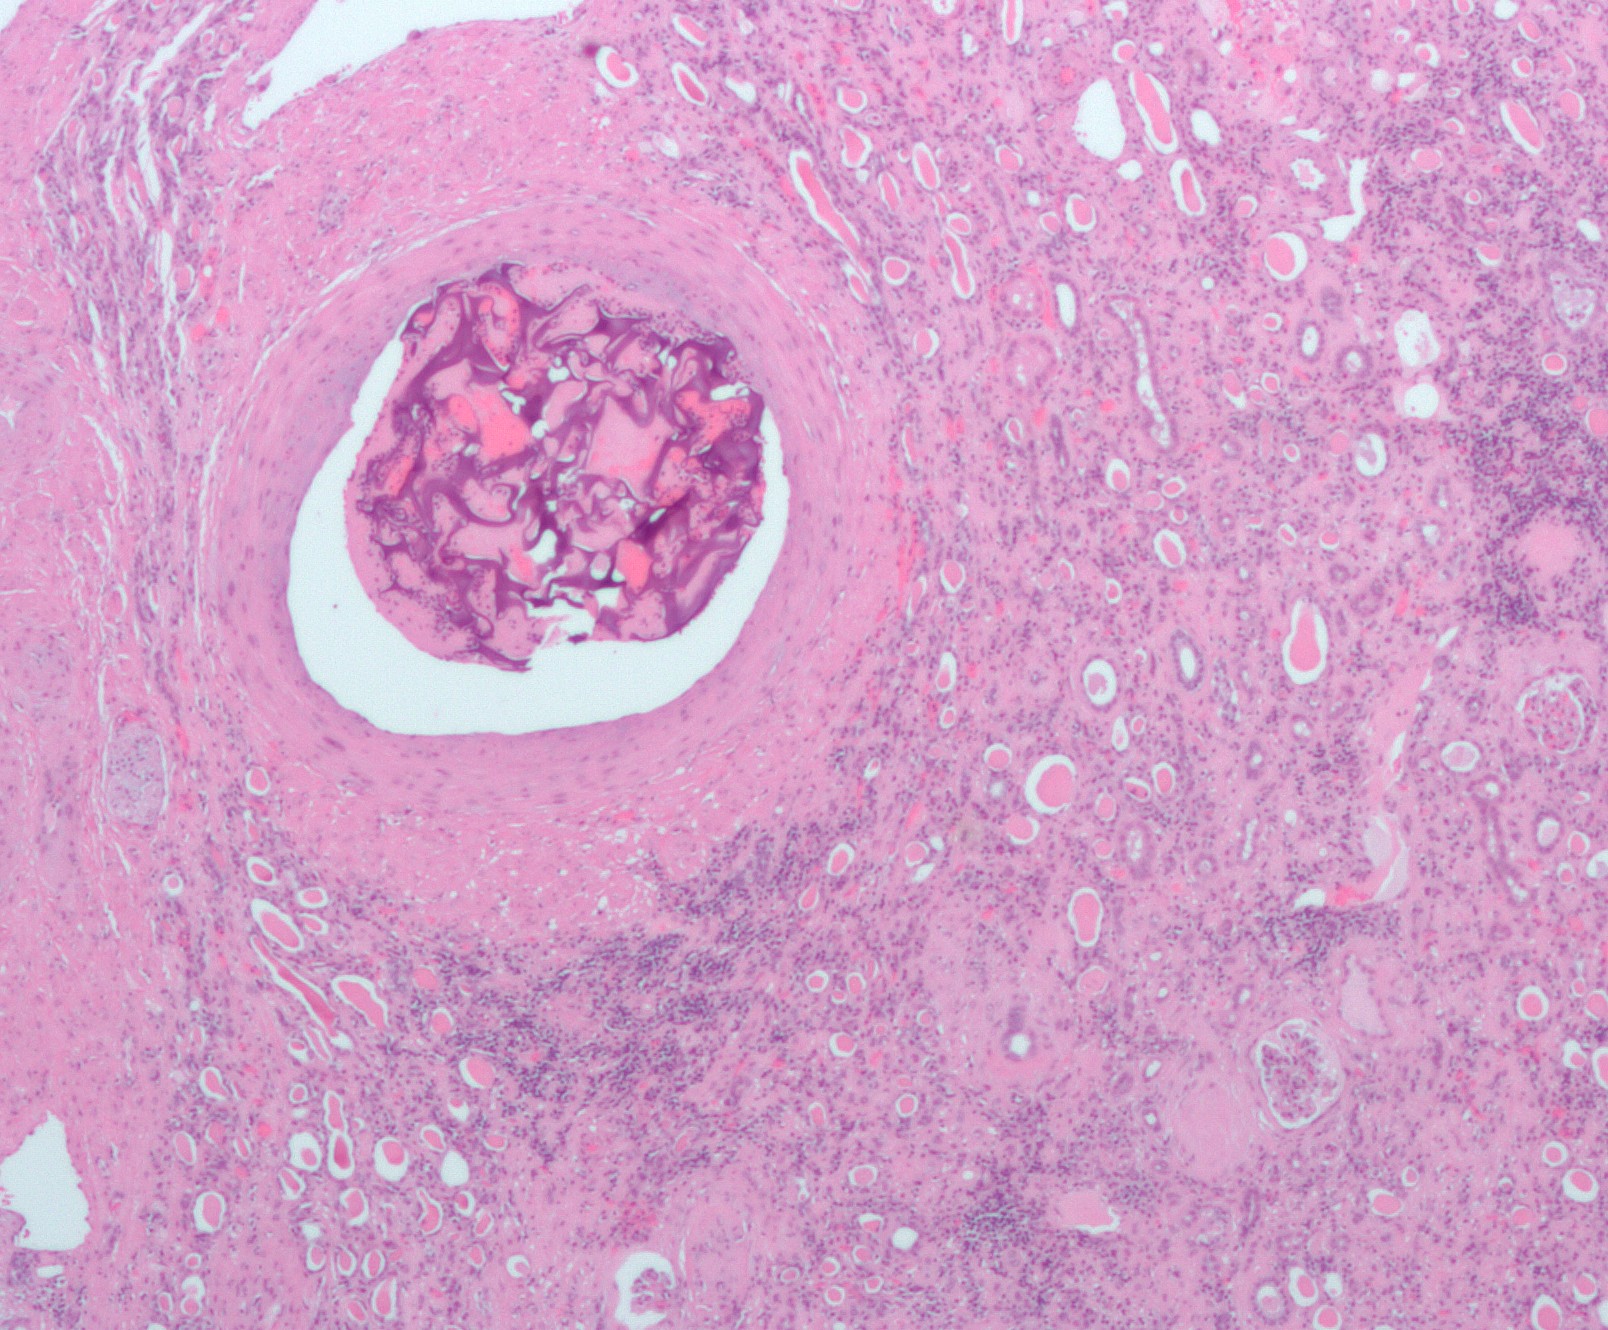

복강 내 이물질은 결국 이물 육아종에 갇히게 된다. 매우 드문 경우로, 잔류 자궁외 임신의 경우 석태아가 형성되기도 하는데, 이는 태아가 너무 커서 재흡수될 수 없고 감염으로부터 주변 조직을 보호하기 위해 석회화되는 것이다.[13]